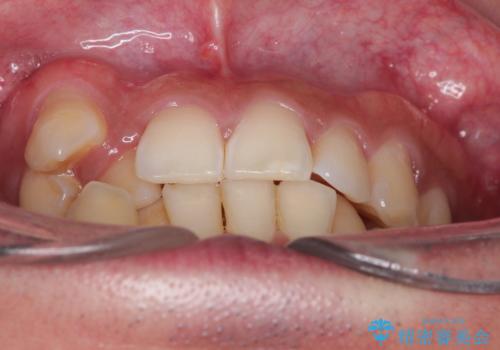

【ワイヤー矯正】八重歯と下の歯の凸凹を治したい

- 主訴:右上の八重歯と、下の歯の凸凹を治したい

上顎右側第一小臼歯と下顎右側第一小臼歯を抜歯しワイヤー矯正を行いました。

右側2級、左側1関係だったため、右側上下第一小臼歯を抜歯し、ワイヤー矯正を行いました。